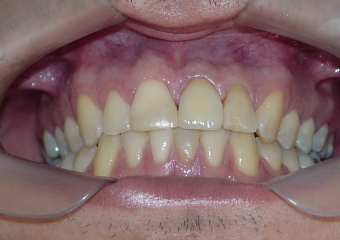

Imagem final do caso terminado em Agosto de 2013

Sorriso final